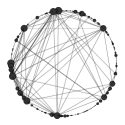

Figure 2 shows the network of the GO:0007399 pathway, related to the nervous system development in the two cohorts. It is clear that several connections among the genes within this pathway are missing in the subjects living in the polluted area (Teplice). Therefore the nervous system development in these children is potentially at risk compared to those living in the not polluted city (Prachatice).

|

|

| (a) Prachatice | (b) Teplice |